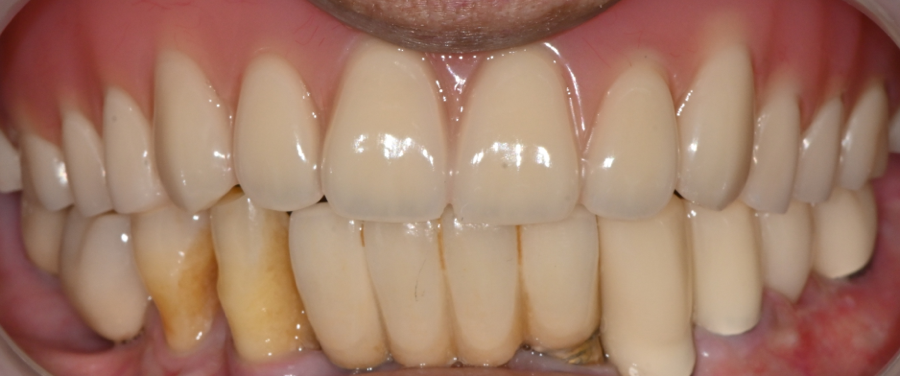

④ 최종 틀니 장착

색상, 높이, 교합을 다시 확인한 뒤

상악 전체틀니를 안전하게 장착했습니다.

장착 직후

“씹는 느낌이 훨씬 안정적이다.”

라고 말씀해주셔서 너무 뿌듯했습니다.